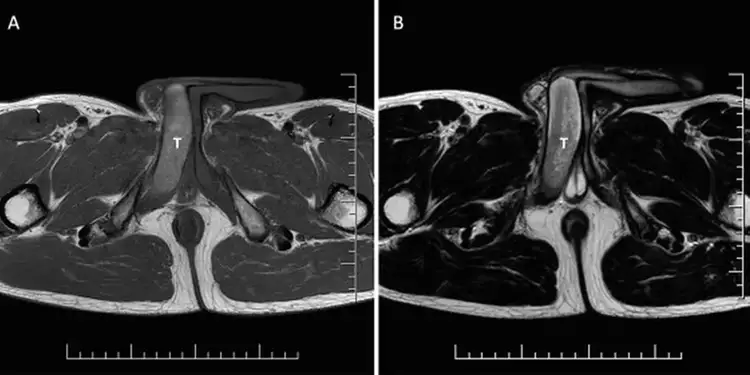

Homem teve dois dias de ereções após corrida é estudado cientificamente

Os pesquisadores consideraram o episódio raro e peculiar já que existem apenas 56 histórias semelhantes registradas no mundo Um homem, de 44 anos, desenvolveu um coágulo sanguíneo no pênis após uma corrida. O inchaço durou dois e o maratonista precisou ser analisado cientificamente. O caso aconteceu na Eslováquia. Os pesquisadores consideraram o episódio raro e peculiar já que existem apenas 56 histórias semelhantes registradas no mundo. […]